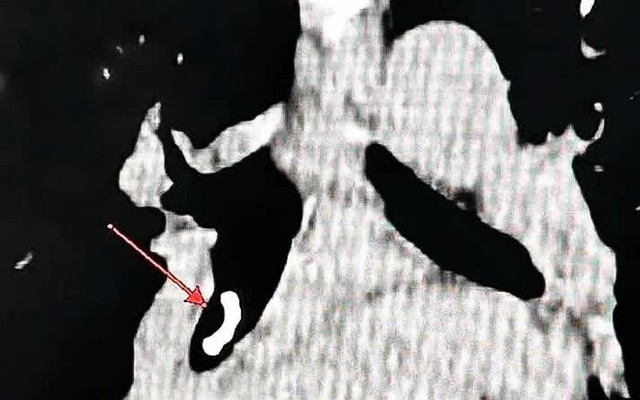

Tại Khoa A1, Bệnh viện Quân y 4, các bác sĩ tiến hành khai thác kỹ tiền sử, đánh giá lại toàn bộ diễn tiến lâm sàng và hướng chẩn đoán trước đó. Trên cơ sở nghi ngờ nguyên nhân hô hấp chưa được phát hiện, người bệnh được chỉ định chụp CT ngực độ phân giải cao và nội soi phế quản.

Kết quả nội soi cho thấy có một dị vật nằm sâu trong lòng phế quản - nguyên nhân gây tình trạng viêm kéo dài, sốt và ho dai dẳng suốt nhiều tuần. Dị vật được xác định là một mảnh xương dài khoảng 20 mm, bám chắc vào thành phế quản.